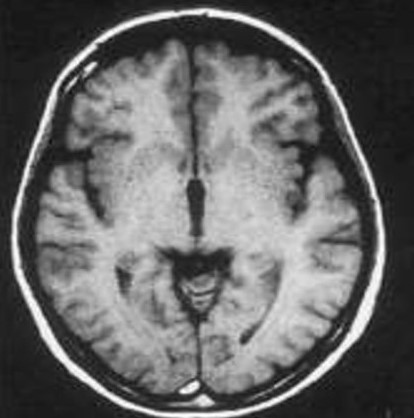

Портальная энцефалопатия